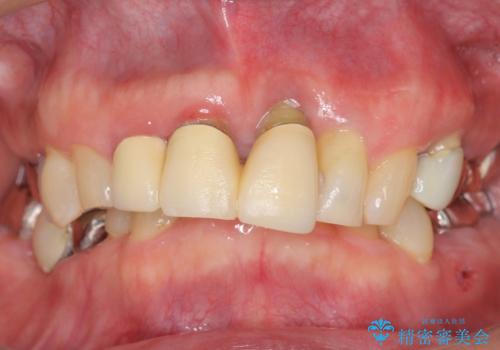

- 左下奥歯の歯ぐきから膿が腫れてきたことを主訴に来院された患者様です。

精査したところ奥歯(左下6)が破折しており、保存不可能と診断されました。

インプラント・入れ歯・自家歯牙移植(親知らずの移植)の選択肢を提案させて頂いたところ、自家歯牙移植をご希望されました。

保存不可能な奥歯(左下6)を抜歯し、機能していない親知らず(左下8)の移植を行いました。